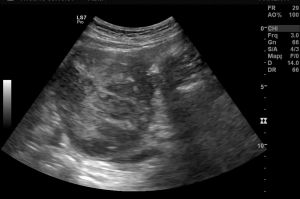

Ad oggi sono state identificate con l’ecografia addominale prevista dal protocollo, 9 neoplasie del parenchima epatico: 5 angiosarcomi (Fig. 1-4) (di cui 2 viventi) e 4 epatocarcinomi (Fig. 5-7) (di cui 1 vivente), successivamente sottoposte a studio TC e tutte confermate dalla diagnosi istologica.

Fig.1. Caso 1 di angiosarcoma epatico

Fig.2. Caso 1 di angiosarcoma epatico